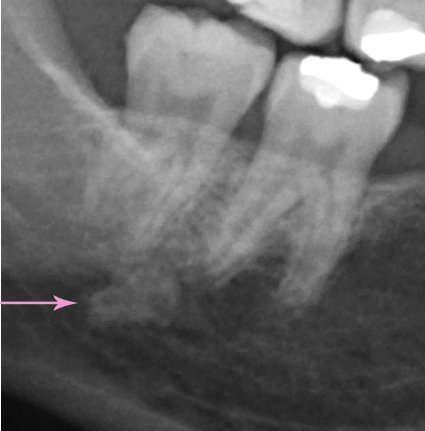

Добрый день. Особых проблем я не вижу, уважаемый пациент. 4.7 зуб необходимо тщательно осмотреть на предмет пригодных тканей для последующего восстановления вкладкой и коронкой, на 4.6 также есть воспаление на верхушке корня, все также необходимо пролечить затем изготовить культевую вкладку и коронку, 3.6 необходимо перелечить, плохая некачественная пломбировка, а также большая по площади пломба, при неблагоприятном исходе может привести к сколу стенки, что в последствии также к потере зуба, 2.6 скорее всего удалится, но еще раз стоит сделать ревизию, 1.6 необходимо перелечить.